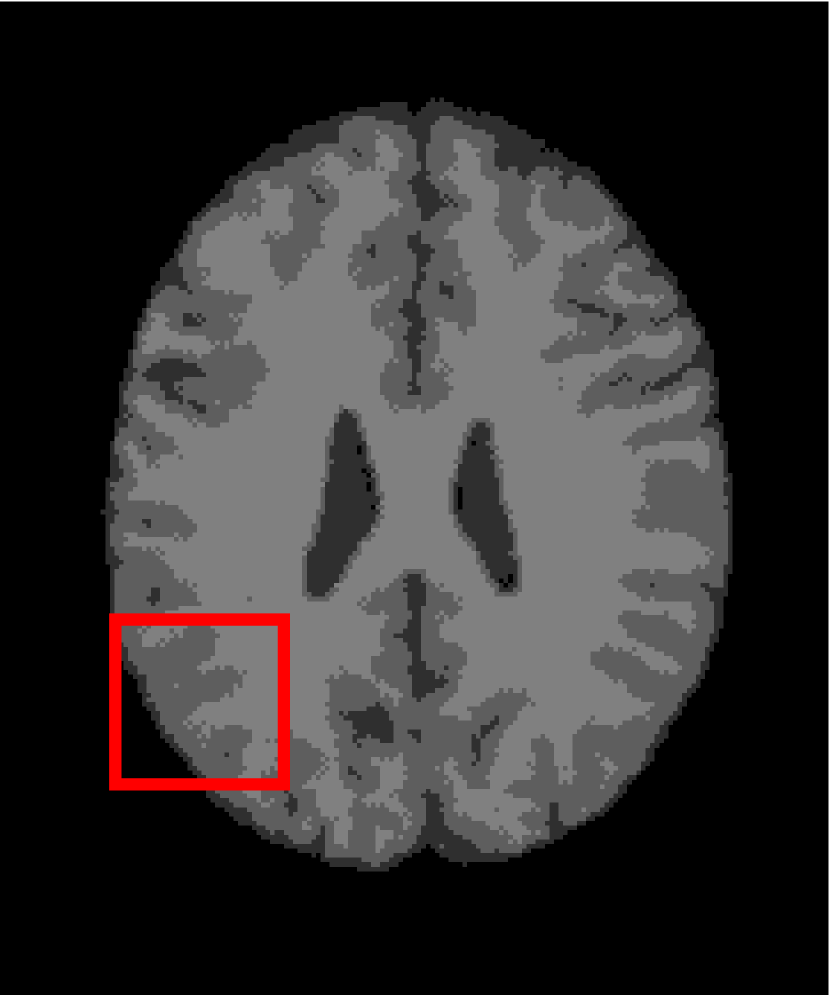

In the second experiments, we segment two medical images coming from a simulated brain database (BrianWeb): http://www.bic.mni.mcgill.ca/brainweb/. The two images are generated by T1 modality with slice thickness of 1mm resolution, 9% noise and 20% intensity non-uniformity. Here, the two images are represented two slices in the axial plane with the sequence of 100 and 110. Moreover, there are golden standard segmentations in the dataset. We set the numbers of clusters to 4. The visual comparisons are illustrated in Figs. 6 and 7.

Figure 6: Segmentation results for the first medical image. From (a) to (l): ground truth, noisy image and results of FCM_S1, FCM_S2, FGFCM, FLICM, KWFLICM, ARKFCM, FRFCM, WFCM, DSFCM_N, and LRFCM.

Figure 7: Segmentation results for the second medical image. From (a) to (l): ground truth, noisy image and results of FCM_S1, FCM_S2, FGFCM, FLICM, KWFLICM, ARKFCM, FRFCM, WFCM, DSFCM_N, and LRFCM.

By focusing on the marked red square in Figs. 6 and 7, we easily find that FCM_S1, FCM_S2, FGFCM and ARKFCM are sensitive to noise. FLICM and KWFLICM are vulnerable to severe intensity inhomogeneity. FRFCM brings overly smooth results due to the use of gray level histograms. WFCM and DSFCM_N cause several contours to change. However, LRFCM acquires clear contours and suppresses noise adequately. Moreover, we find that the segmentation result of LRFCM is closer to ground truth.